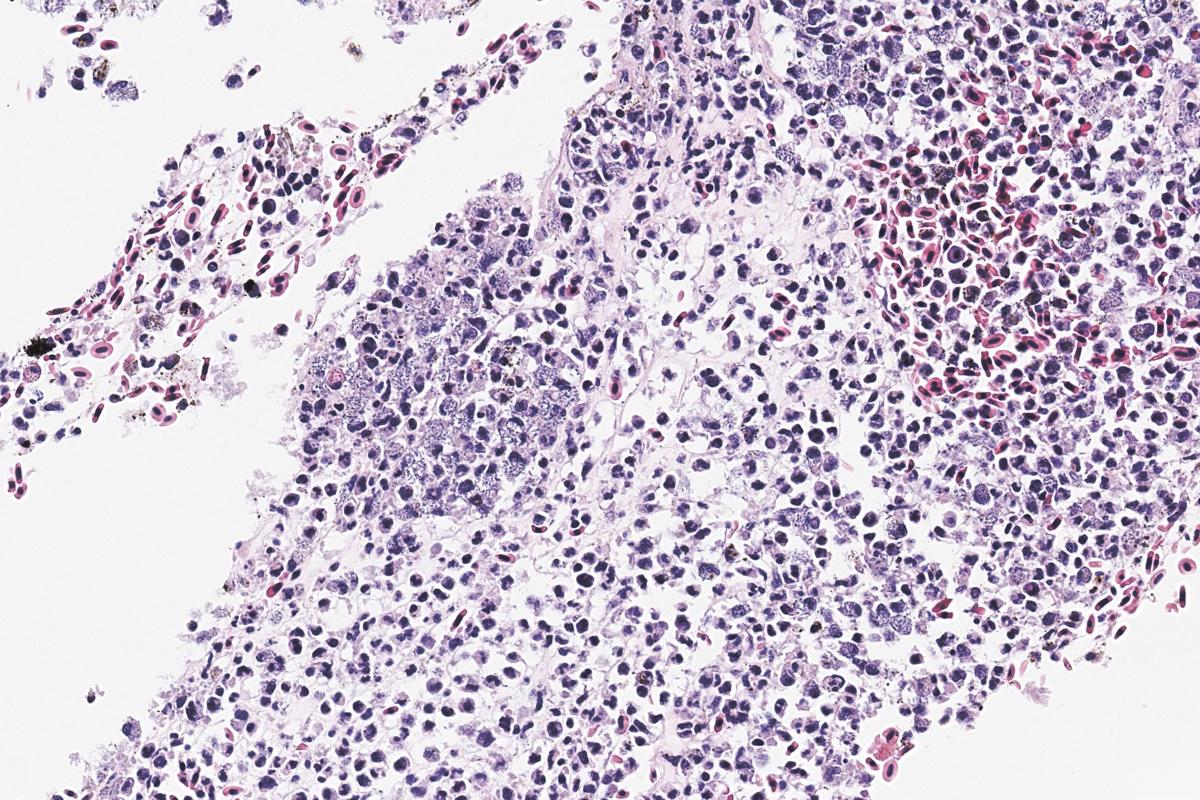

Bilde 3: Histologisk snitt. HE-farging. Hud med bakteriell dermatitt (pil), fra en sak med påvist klassisk vibriose.

Vibriose er en sykdom som rammer mange ulike fiskearter, både villfisk og oppdrettsfisk i sjøvann og brakkvann. Sykdommen forårsakes av bakterier i slekten Vibrio, og utbrudd skjer ofte i forbindelse med stress, for eksempel ved håndtering, og særlig når vanntemperaturen er høy.

Vaksine mot Vibrio anguillarum gir vanligvis god beskyttelse. Likevel kan det forekomme sykdomsutbrudd, spesielt under ugunstige forhold.

I 2024 ble det rapportert enkelte tilfeller av vibriose hos regnbueørret. Det ble påvist systemiske infeksjoner med V. anguillarum, men i de fleste tilfellene var det en bakterie som lignet V. ordalii som dominerte.

Det kliniske bildet viste økt dødelighet, hudblødninger og tegn til sepsis med petekkier i flere organer. Det er også vanlig med utflytende milt ved vibriose hos regnbueørret.